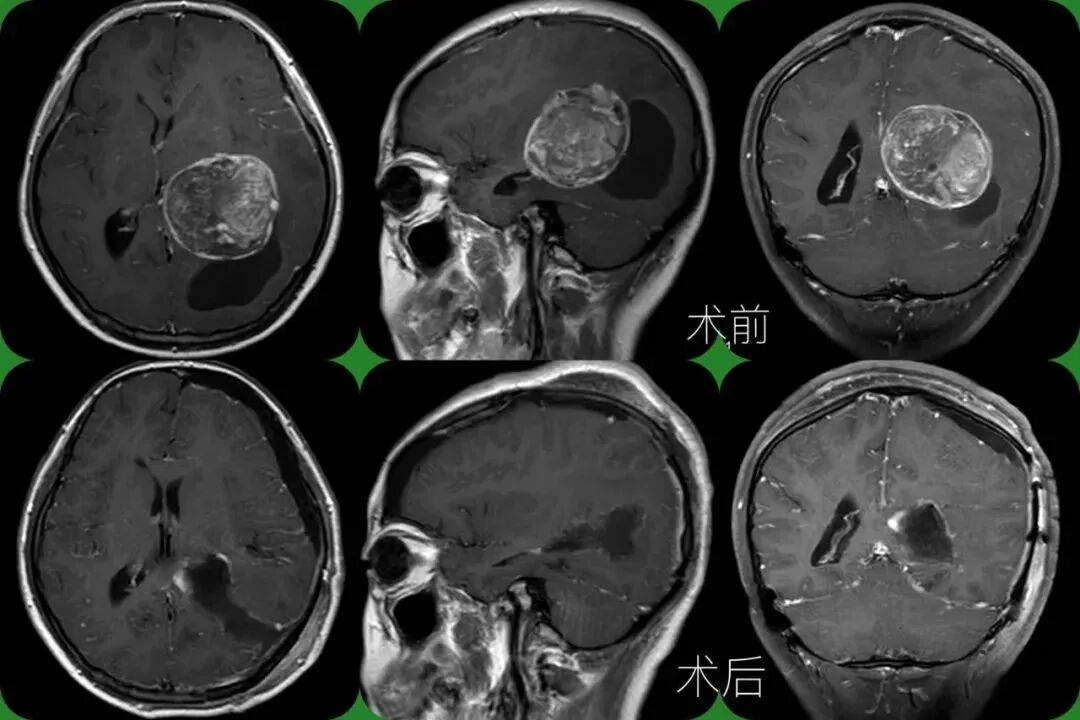

13 岁女孩,双眼视力持续性下降,一直以为是近视,直至出现头疼,就诊确诊为 6x5x5cm 脑膜瘤。

昆明三博脑科医院院长张永力介绍:「 这三个案例病人年龄不一样,患的肿瘤不一样,但都有一个共同点,就是延误了早期诊断,觉得眼睛的问题与脑肿瘤扯不上关系,长期去看耳鼻喉科和眼科,等症状加重时才发现是脑部的问题,发现时脑瘤已经长得很大,不但让治疗、后期维养恢复变得更加困难,同时也增加了治疗费用,甚至的有的患者虽然摘除了肿瘤,但视力恢复到正常的机会已大为降低, 给家人及患者都带来巨大的困扰。」